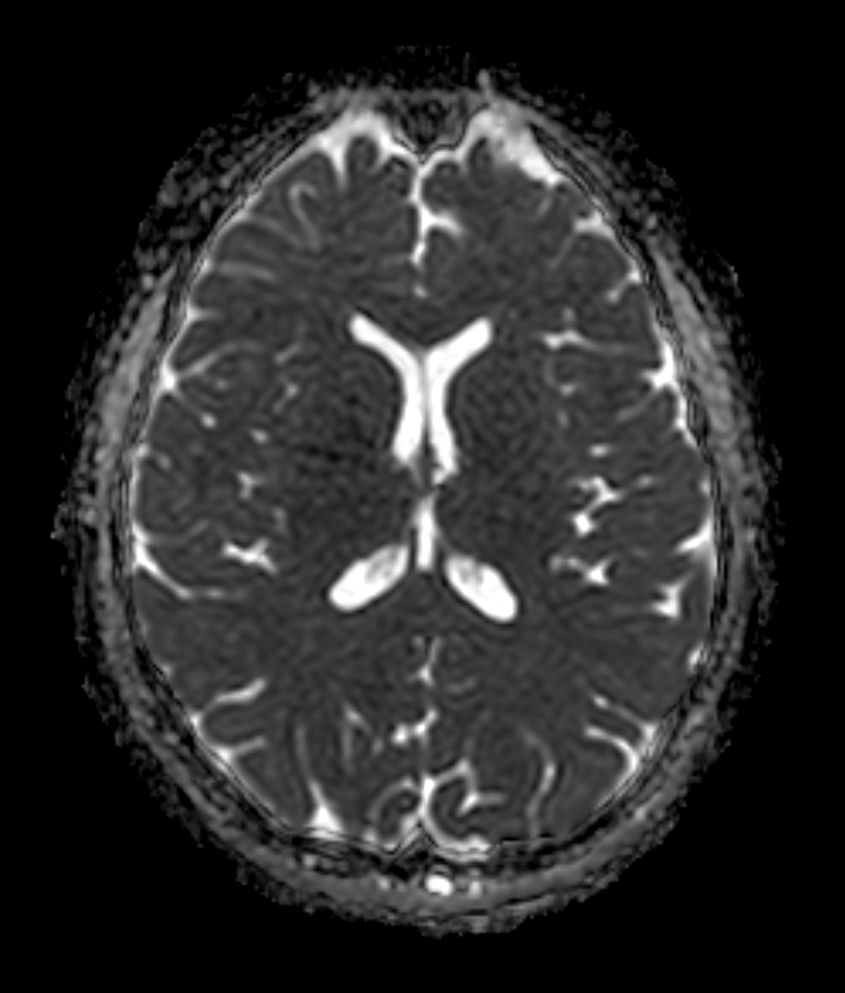

Axial SWIp (Modulus)

-

Axial SWIp (minIP)

Axial SWIp (Phase)